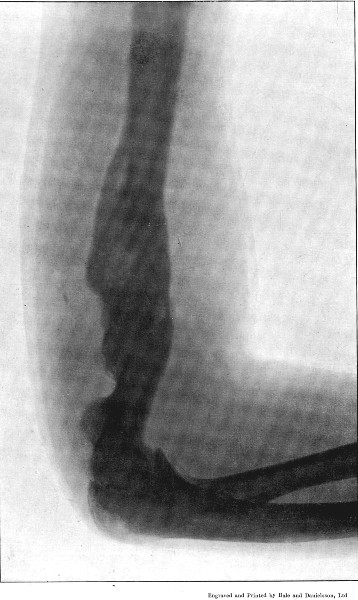

I am greatly indebted to my former colleague Mr. Cheatle for two of the illustrations of wounds, and for permission to quote some of his other experience, and to Mr. Henry Catling, to whose skill I owe the majority of the skiagrams of the fractures under my observation at Wynberg and elsewhere.

3. Punctured Fracture of Clavicle162

4. Comminuted Fracture of Shaft of Humerus180